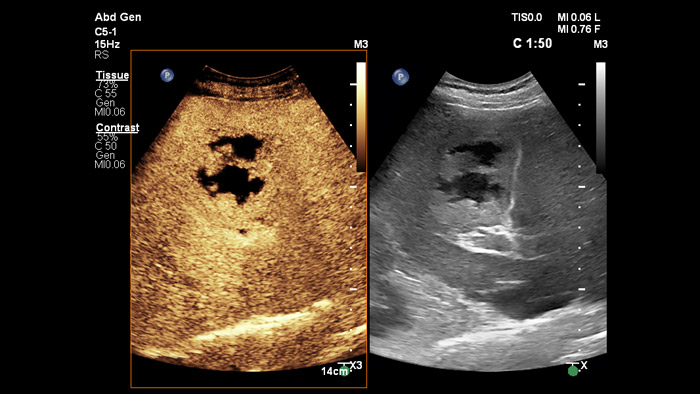

Les agents de contraste échographiques peuvent transformer le rôle de l'échographie dans l'évaluation du foie en permettant d'étudier les schémas de rehaussement des lésions hépatiques suspectes en temps réel pour un diagnostic plus rapide et plus sûr.